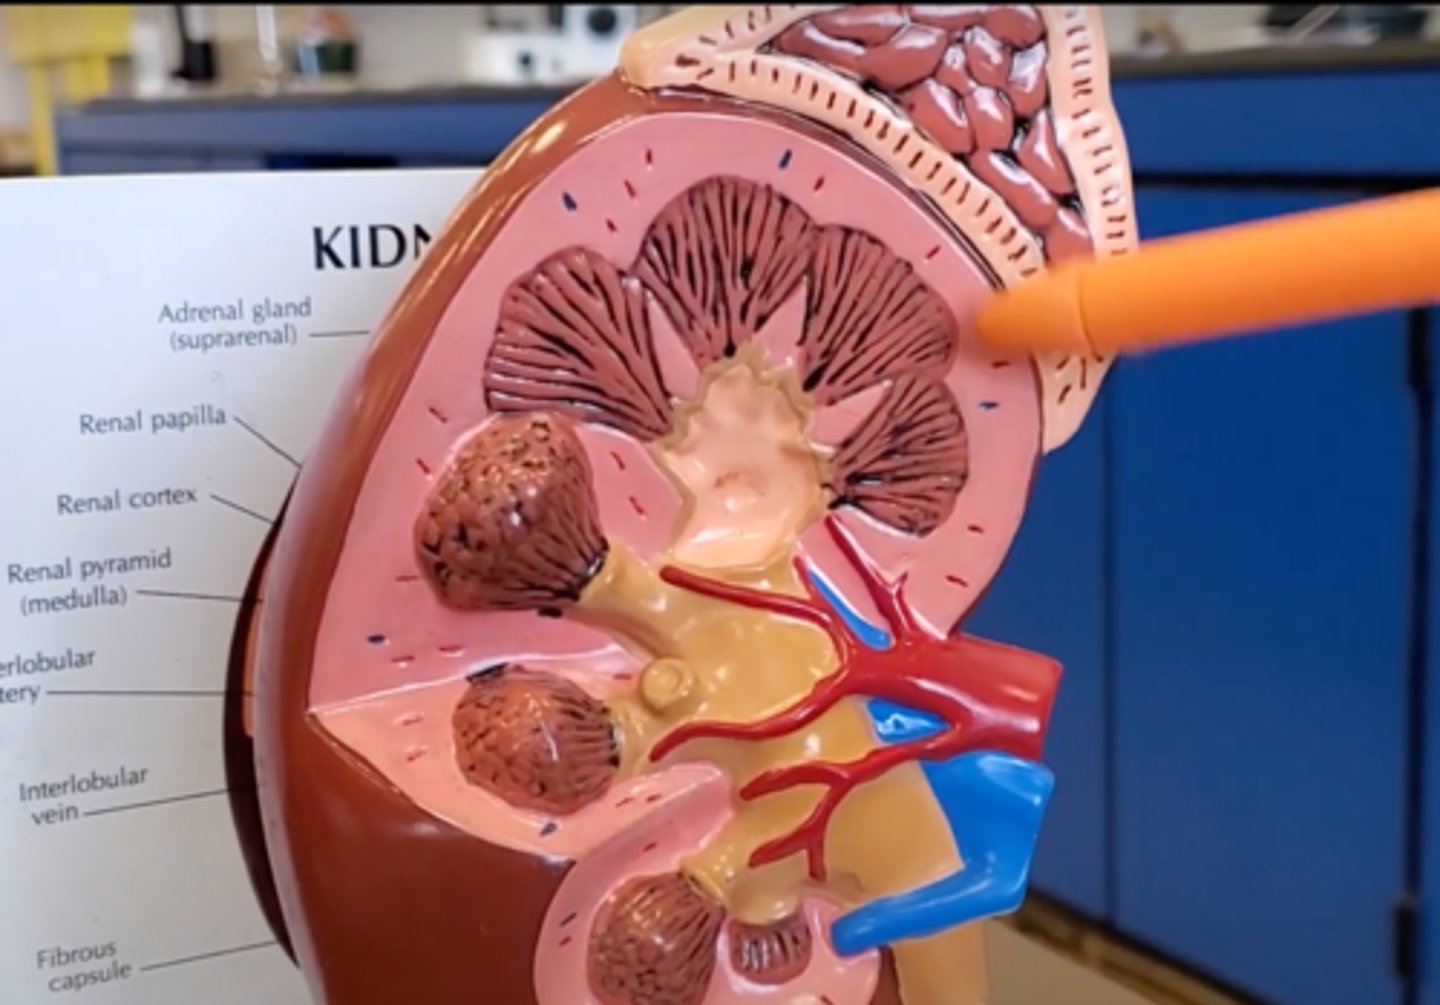

renal pyramid

2

renal column

3

cortex

outer layer of the kidney

ureter

A duct leading from the kidney to the urinary bladder.

nephron

the functional unit of the kidney

Adrenal gland

A pair of endocrine glands that sit just above the kidneys and secrete hormones that help arouse the body in times of stress.